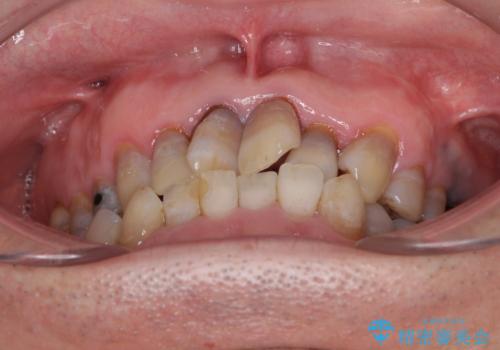

上顎の狭窄歯列 インビザラインによる拡大矯正

- 前歯の叢生と臼歯のクロスバイトを気にして来院された患者様です。

急速拡大装置による上顎の側方拡大を行い、その後はインビザラインより歯列を改善することとしました。

20代後半以降の男性は上顎骨の側方拡大処置の成功率が低く、今回も骨を拡大することができませんでした。

しかしながら、歯列を側方に拡大することができ、その後はインビザラインにて叢生を解消することができました。